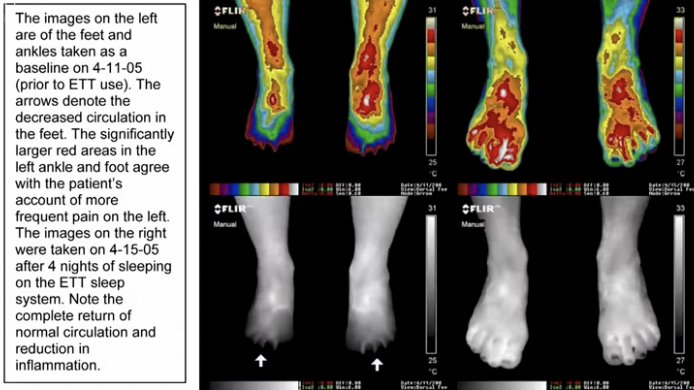

Sursă photo: Gaia